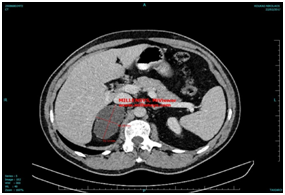

A localized specific adrenal CT scan revealed a hypodense, clear delimited mass of the right adrenal gland, with dimensions of 8x4x6,6 cm, without contrast enhancement, measured of 11 Housefield units., mainly characterized by the radiologist as adenoma see Figure 1.

Figure 1 Radiologic Findings A localized specific adrenal CT scan.